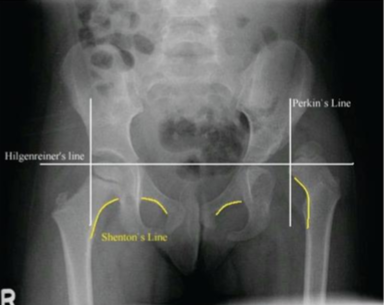

Classification - Developmental Dysplasia of Hip

congenital, depends on cause

types

dislocated = FH completely out of socket

disloc-able = high chance of dislocation

sublux-able = FH is loose in socket

Etiology - DDH

structural defects in the acetabular region

risk factors: first born, females (increased progesterone), breech position

Rad - DDH

AP views

evaluated with Perkin’s, Hilgenreiner’s, Shenton’s line